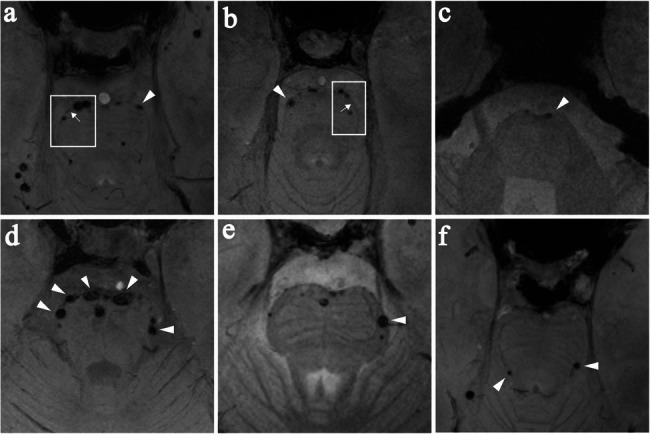

Materials and methods: This cross-sectional study included seven patients with hHTRA1-CSVD, twenty-seven patients with CADASIL and twelve patients with sporadic CSVD. All participants underwent 7.0T magnetic resonance imaging (MRI). The "pons chocolate chip sign" was defined as round or ovoid hypointense dots (≥ 2 mm in diameter) surrounding the pons on T2*-weighted gradient echo images. The number of chocolate chips was independently assessed by two blinded neurologists. Diagnostic performance was evaluated using receiver operating characteristic (ROC) curve analysis, with genetic diagnosis as the gold standard.

Results: The "pons chocolate chip sign" was found in 5/7 patients with hHTRA1-CSVD, compared to 2/27 in CADASIL and 0/12 in sporadic CSVD. ROC analysis revealed that it exhibited good discriminatory capability for hHTRA1-CSVD (area under the curve [AUC] = 0.84, 95% confidence interval [CI]: 0.63-1.00, P = 0.004). At an optimal cutoff of chocolate chips ≥ 1, the sensitivity, specificity, positive predictive value (PPV), negative predictive value (NPV), and Youden index were 71.42%, 94.87%, 71.42%, 94.87%, and 0.66, respectively. When the cutoff was increased to ≥ 3 chocolate chips, the specificity improved further, reaching 100%.